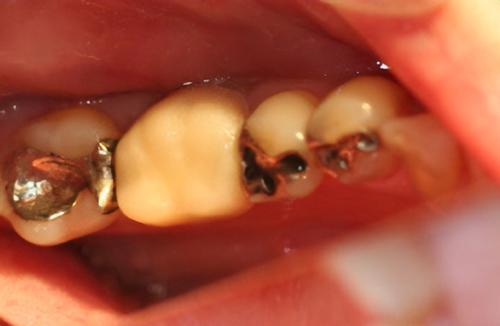

噛み合う歯にやさしい

レジンという樹脂とセラミックで作られ、セラミックほど硬くはなく、噛み合う歯にやさしいと言えます。セラミックを含むことで、十分強度を得ており自然な色調を再現でき、また変色もしにくくなっています。

虫歯だけを削り、従来の変色してしまう材料ではなく、セラミックを50%含む材料で自然な色調と艶を再現。

術前

-

術後